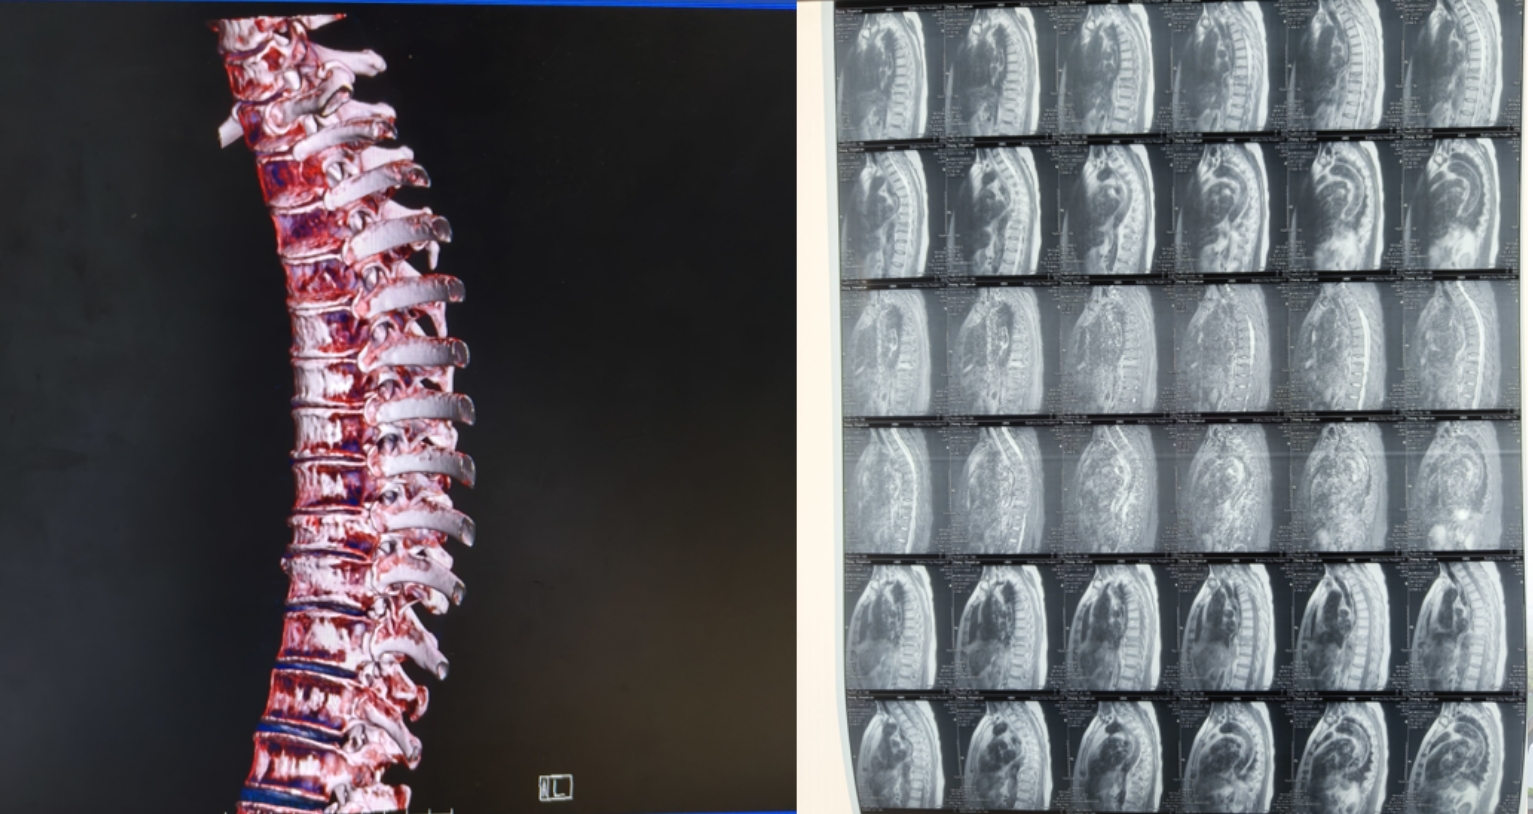

做了个叫做MRI的高级检查,结果显示她的胸椎有些老化变化,第9节胸椎骨头被压扁了,里面还有些水肿。

面对诊断结果,张奶奶和家人经过深思熟虑,决定勇敢接受手术治疗。他们相信,通过现代医学的力量,能够有效解决胸椎的病理性骨折问题,阻止疼痛的进一步侵扰,重获生活的舒适与自由。